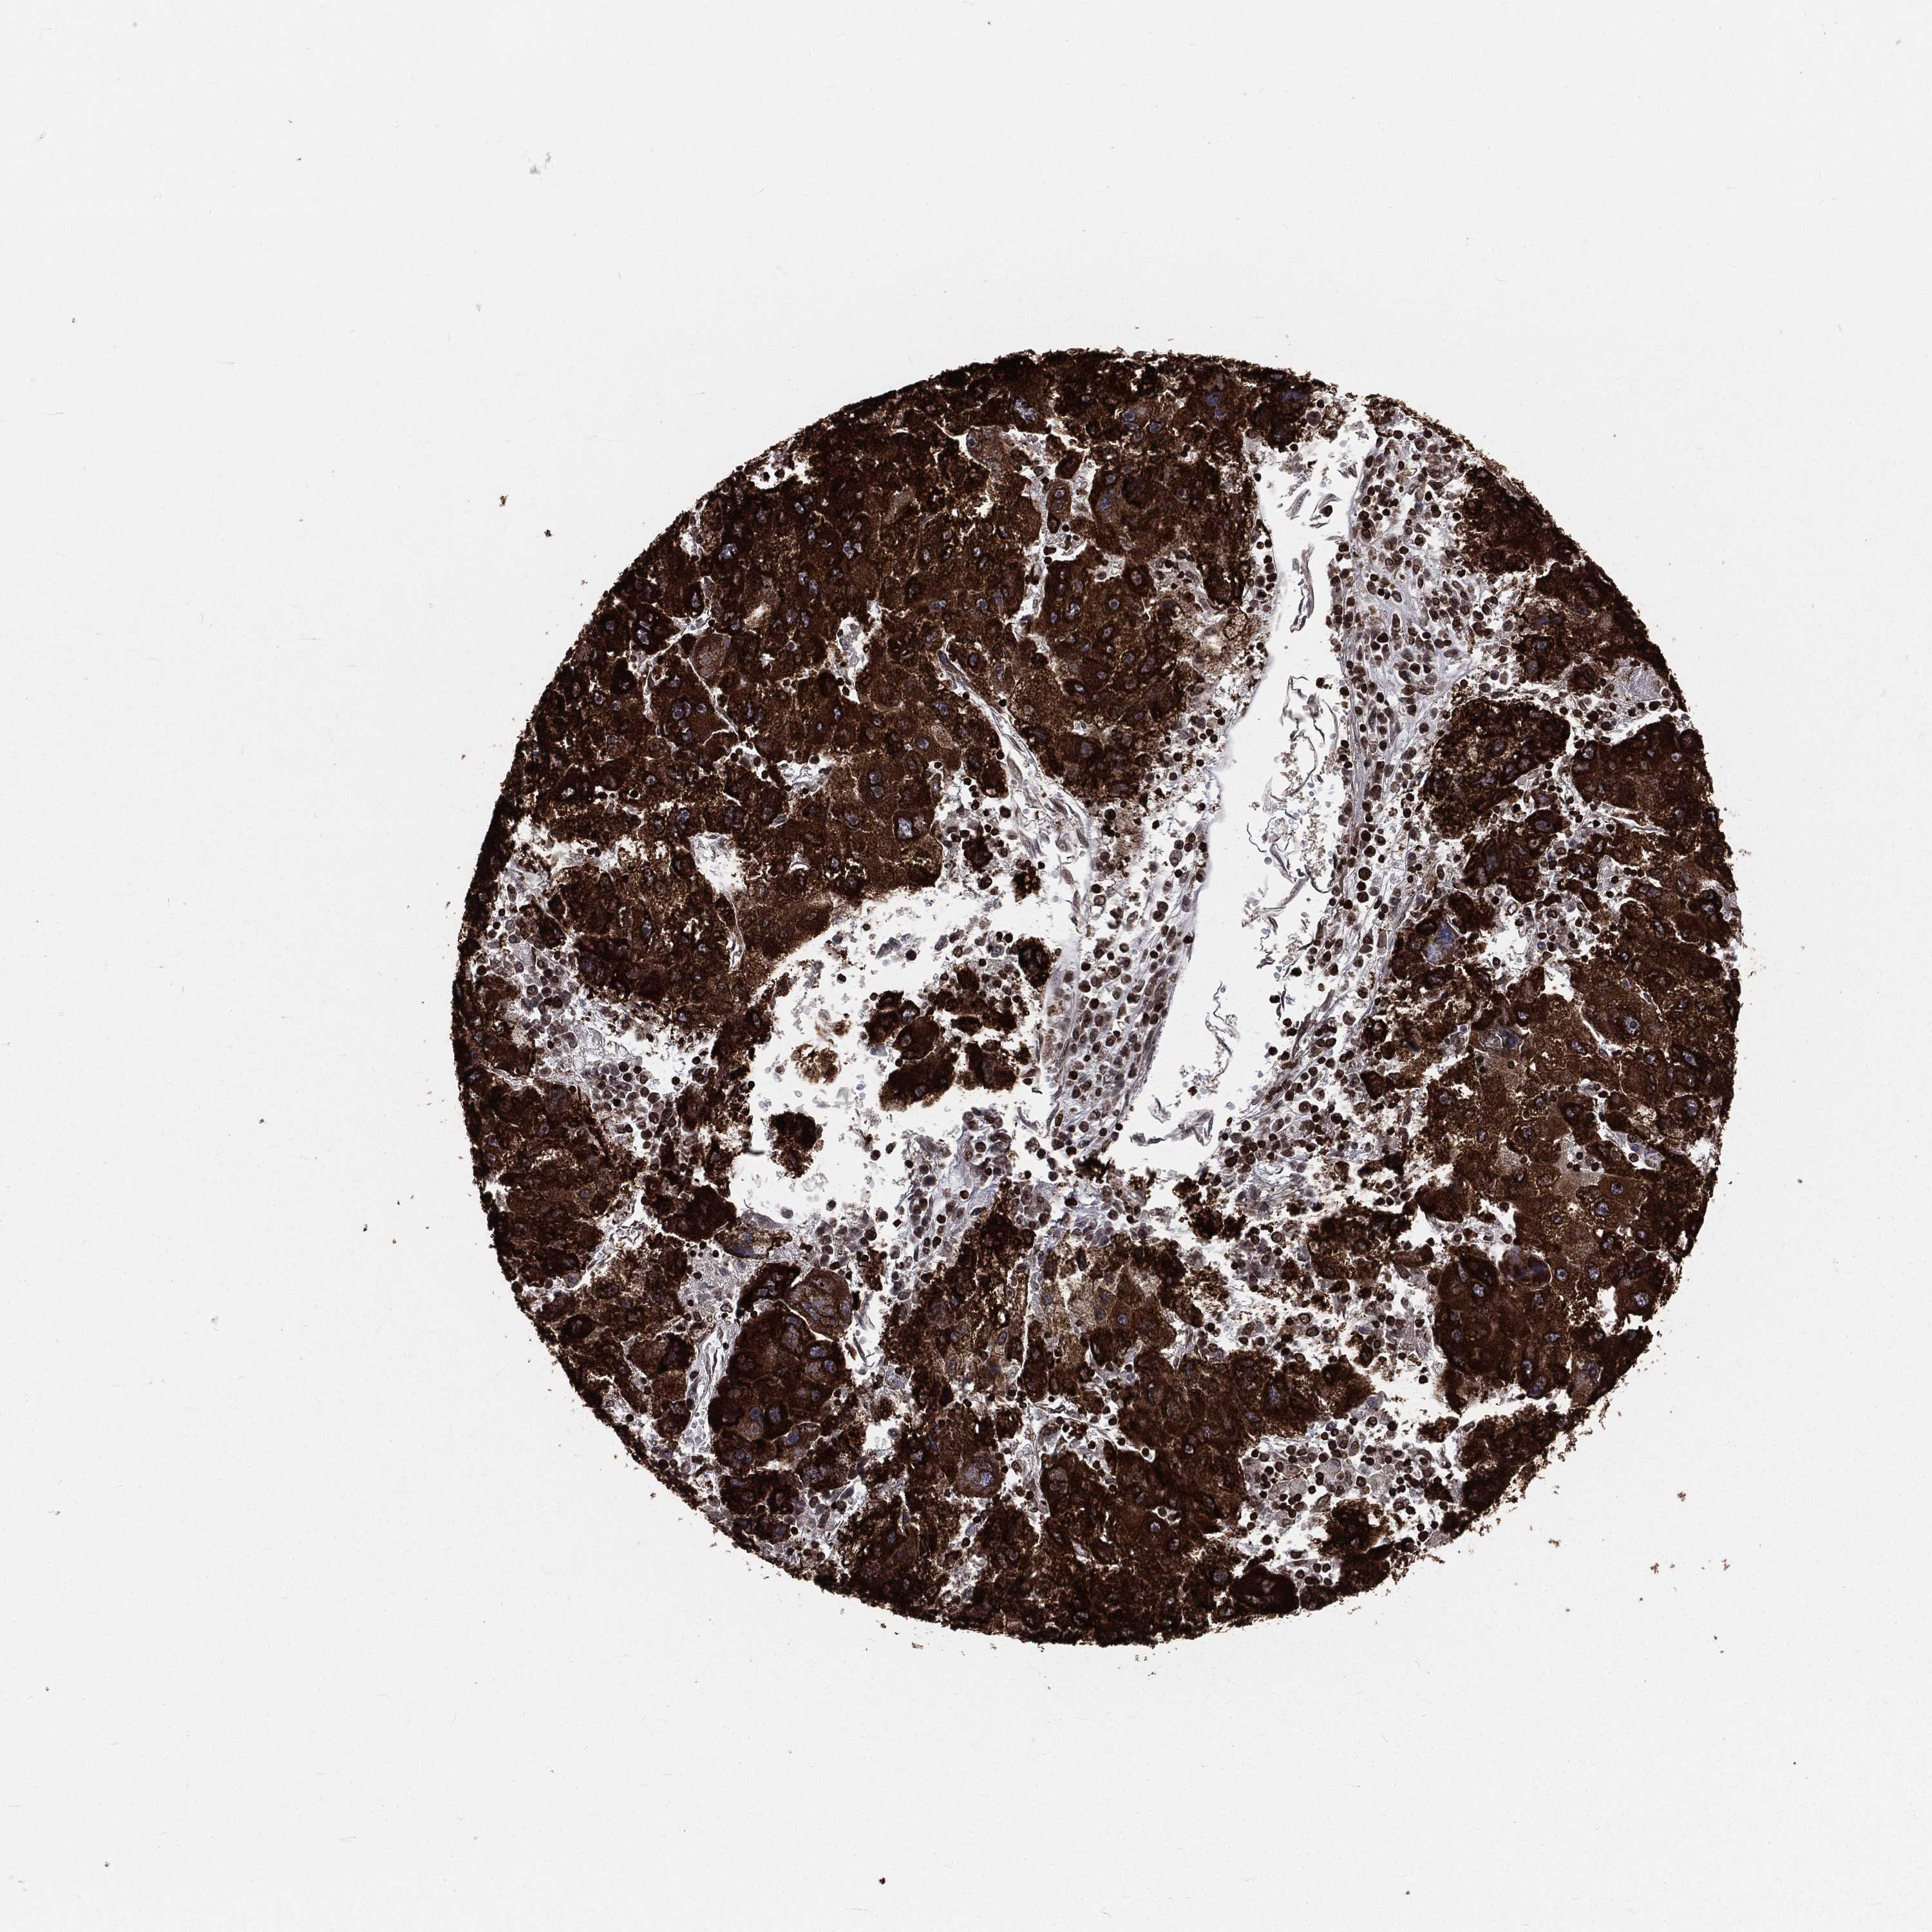

LIVER CANCER - Protein expressioni

A mouse-over function shows sample information and annotation data. Click on an image to view it in a full screen mode. Samples can be filtered based on level of antibody staining by selecting one or several of the following categories: high, medium, low and not detected. The assay and annotation is described here.

Note that samples used for immunohistochemistry by the Human Protein Atlas do not correspond to samples in the TCGA dataset.

Antibody stainingi

Antibody staining in the annotated cell types in the current human tissue is reported as not detected, low, medium, or high, based on conventional immunohistochemistry profiling in selected tissues. This score is based on the combination of the staining intensity and fraction of stained cells.

Each image is clickable and will lead to virtual microscopy that enables deeper exploration of all samples and also displays staining intensity scores, fraction scores and subcellular localization as well as patient and tissue information for each sample.

Antibody HPA049840

Antibody HPA062236

Staining

High

Medium

Low

Not detected

Intensity

Strong

Moderate

Weak

Negative

Quantity

>75%

75%-25%

<25%

None

Location

Nuclear

Cytoplasmic/membranous

Cytoplasmic/membranous,nuclear

Cholangiocarcinoma

Carcinoma, Hepatocellular, NOS